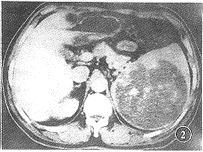

图2 CT增强示肿物部分边缘及肿物内等密度灶不均匀强化,肿物边界更加清晰,残留的脾实质呈正常强化表现